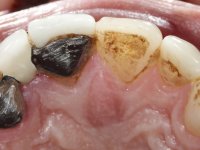

Fifty year old male patient, non-smoker. Carries a Maryland Bridge replacing tooth 2.2. "Maryland wings" are metallic and the dental surfaces in contact with them are infiltrated. Tooth 2.1 had a feldspathic ceramic veneer covering the vestibular surface. Tooth 1.2 presented a feldspathic ceramic veneer with exposed cervical margin. The edentulous space corresponding to tooth 2.2 is narrow and tall. Patient presents an open anterior bite, good oral hygiene and reasonable periodontal health.

Arcade prints were made with irreversible hydrocolloid, for the lab to prepare an acrylic provisional bridge, with tooth 2.1 as abutment and tooth 2.2 as cantilever pontic. A palatal support was made to be bonded with the palatal surface of tooth 2.3. After removal of the Maryland bridge and the vestibular veneer from tooth 2.1, the dental abutment was re-prepared by making the cervical finish line intrasulcular. The provisional bridge made in the lab was relined on the mouth with self-curing acrylic and composite resin. During 6 weeks the soft tissues were worked and stabilized, preparing the consultation for impression. In this session, gingival separation was performed with kaolin paste, using the provisional bridge to compress the material into the gingival sulcus. Impression was performed using wash technique, and the provisional bridge was placed. At the end of the consultation, an impression was made from the provisional bridge placed in the mouth, using irreversible hydrocolloid. The patient had approved the aesthetics of the provisional. This information was passed on to the lab, where the work followed a silicone index, based on the shape and arrangement of the provisional bridge, approved by the patient. The cantilever bridge was built with a Zr infrastructure, with particular care in designing the connector. After being tried and approved by the patient, the prosthetic was cemented in the mouth with resin modified glass ionomer.